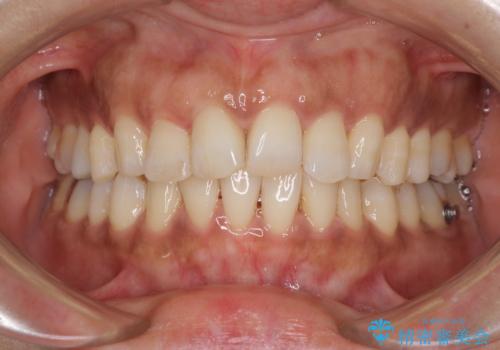

- 上下前歯のデコボコ改善をインビザラインにて行いたいとのことで来院された患者様です。

インビザラインをご希望のことで、IPR(歯と歯の間を削る)などによりスペースを獲得して、排列していくこととしました。

骨格的に上下顎が左右にずれていたため、正中位置は現状を維持したまま歯列不正を解消していくことになります。

なかなか装着時間が守れず、後戻りを繰り返しながら治療を進めたため、インビザライン治療期間期限ギリギリの5年弱の期間を要しました。